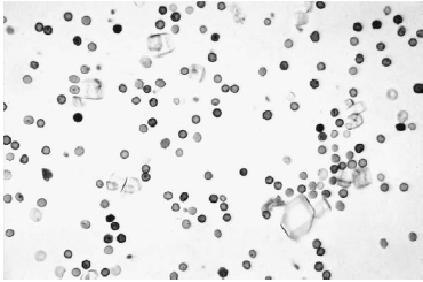

Sedimento urinario de un gato con CIF, se evidencia la presencia de células rojas y escasas células blancas. La presencia de cristaluria no indica que es la causa de los signos clínicos. Un urotelio normal no debe verse afectado por la presencia de cristales (Hostutler et al)

Muchas veces el laboratorio reporta la presencia de bacterias, cuando en realidad no están presentes. Este problema es común en gatos y es causado principalmente por el material particulado, como pequeños cristales, debris celulares y gotitas lipidicas que exhiben movimiento browniano y pueden confundirse con bacterias.

En el sedimento se pueden encontrar una pequeña cantidad de células blancas. Una orina diluida con piuria o piuria significativa (>5 células blancas por campo) independiente de la gravedad especifica de la orina requiere de cultivo urinario y antibiograma de orina recolectada por cistocentesis.